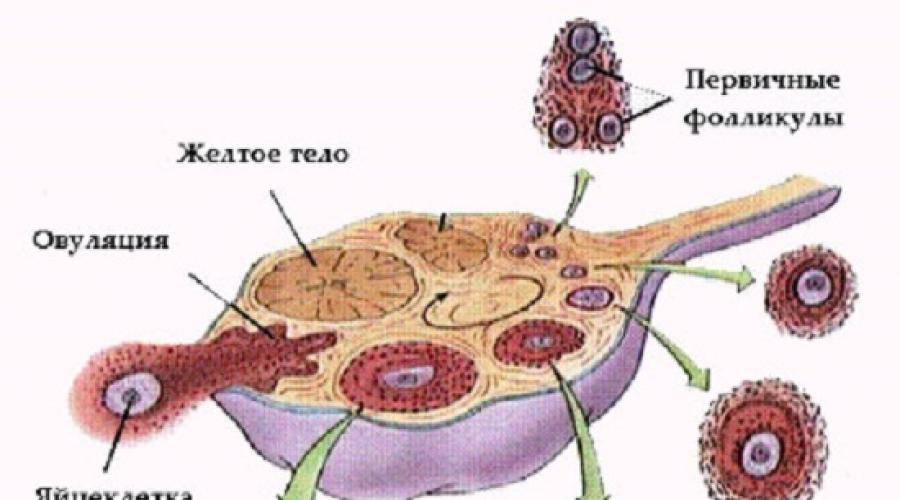

Созревание фолликула в яичнике: этапы и процессы